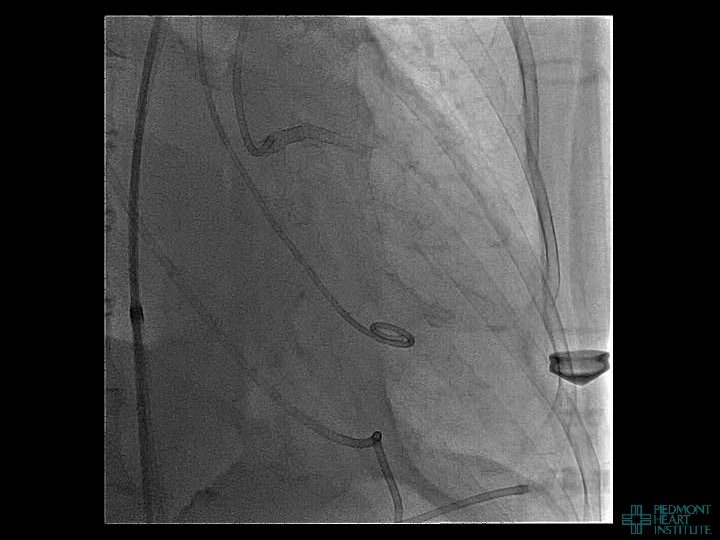

Coronary Perforation Methods of Patient Management • Dual Catheter (‘Ping Pong’) Technique • Prolonged

Coronary Perforation Methods of Patient Management • Dual Catheter (‘Ping Pong’) Technique • Prolonged balloon inflation and covered stents • Reversal of anticoagulation — Know contradictions to protamine sulfate for UFH; Avoid bivalirudin, LMWH — Reserve GP 2 b 3 a inhibition until successful crossing and wire change-out Embolization • — Coil, gelfoam, methacrylate, autologous blood/fat • Microcatheter Occlusion • Confirmation of successful management — Contralateral injection — Right heart catheterization — Echocardiogram — Contrast echocardiography